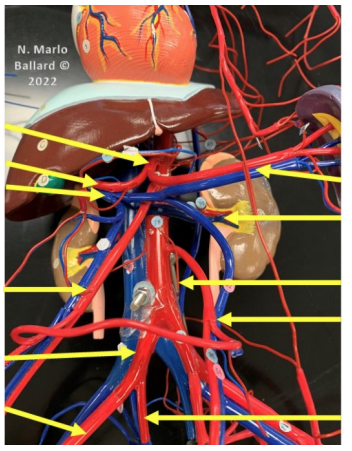

Superarenal vein

Drains blood from the adrenal (suprarenal) glands

Right suprarenal vein → inferior vena cava

Left suprarenal vein → left renal vein

Important asymmetry between right and left sides

Which vessels join to form the IVC

Formed by the union of the Right common iliac vein and Left common iliac vein